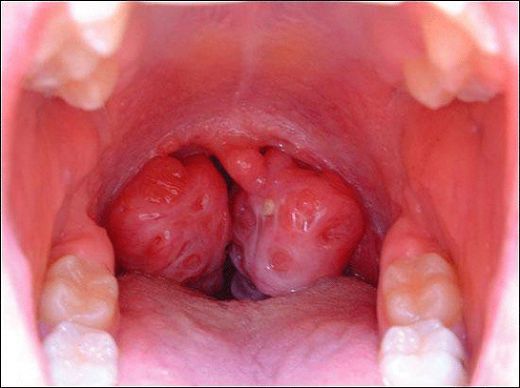

Bademcik İltihabı Nedir?Bademcik iltihabı, genellikle viral veya bakteriyel enfeksiyonlar sonucunda bademciklerin iltihaplanmasıdır. Bademcikler, boğazın arka tarafında bulunan ve vücudu enfeksiyonlara karşı koruyan lenfatik dokulardır. Bu durum, genellikle çocuklarda daha sık görülür, ancak her yaş grubunu etkileyebilir. Bademcik iltihabı, boğaz ağrısı, yutma zorluğu, ateş ve genel bir rahatsızlık hissi ile kendini gösterir. Bademcik İltihabının Belirtileri Bademcik iltihabının belirtileri genellikle şunlardır: